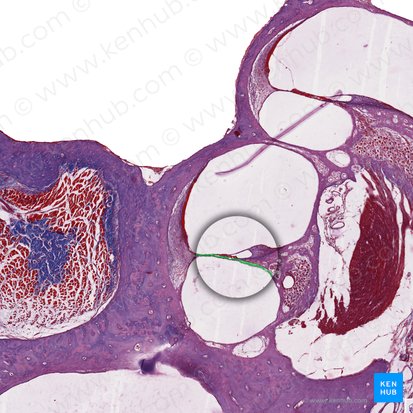

Die Cochlea besteht aus drei flüssigkeitsgefüllten Gängen: Den Scala vestibuli und tympani mit Perilymphe und der Scala media mit Endolymphe.

Chochlea - anterior

Für die Umwandlung weitergeleiteter Schallwellen in akustische Signale ist das Corti-Organ verantwortlich. Es befindet sich in der Scala media auf der Basilarmembran und enthält die inneren und äußeren Haarzellen.

Diese Sinneszellen besitzen Zilien, die durch Tip Links (Proteinfäden) miteinander verknüpft sind und durch die Wirkung der Schallwellen gereizt werden. Dabei kommt es zu einer Auslenkung der Zilien, die die Tip Links in Spannung bringt. Dieses Signal leitet die Öffnung von Ionenkanälen in der Zellmembran und die Veränderung der Membranpotentiale ein.

An den inneren Haarzellen setzen außerdem afferente Fasern des Ganglion spirale und an den äußeren Haarzellen efferente Nervenfasern an, die den N. vestibulocochlearis bilden.

Cochlea II - anterior

Bei Luftleitung werden die Schallwellen über das ovale Fenster an die Cochlea übertragen, wo eine Signaltransduktion stattfindet. Durch die eintretenden Schallwellen entsteht eine Druckwelle, die zu einer Volumenverschiebung der Flüssigkeiten und damit zu einer Schwingung in den Gängen der Cochlea und auch der Basilarmembran führt. Diese breitet sich als Wanderwelle bis zum Helicotrema, dem Endpunkt der Cochlea, aus.

Durch die Schwingung der Basilarmembran kommt es zu einer Reizung der inneren Haarzellen des Corti-Organs. Damit ist gleichzeitig eine erste Frequenzanalyse aufgrund der Formveränderung der Basilarmembran verbunden.

Je nach lokaler Beschaffenheit (Breite, Stabilität) gibt es auf der Basilarmembran spezifische Orte, an denen bestimmte Frequenzen eine maximale Reizung und somit eine maximale Schwingungsamplitude verursachen (Frequenz-Ort-Abbildung).

Corti-Organ - Histologie

Diese Resonanzfrequenz erregt auch die dortige, für sie spezifische, innere Haarzelle maximal. Bei Frequenzgemischen werden an mehreren Orten auf der Basilarmembran Haarzellen maximal erregt. Dabei entstehen Membranpotentiale an den inneren Haarzellen, welche die Schwingung der Basilarmembran verstärken.

Durch diesen cochleären Verstärker werden Signale 100-fach verstärkt an die Hörbahn weitergeleitet. Damit können Frequenzen letztlich besser differenziert werden.